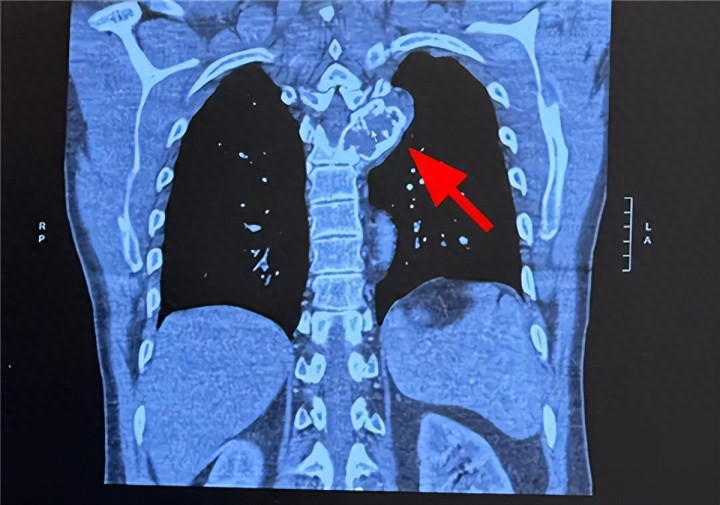

AI工夫对海量医学文件、基因数据及病灶信息进行高效分析,精确识别出了FAP成纤维细胞活化卵白这一要津诊疗靶点,还实时革命了肺部病灶的误诊问题。